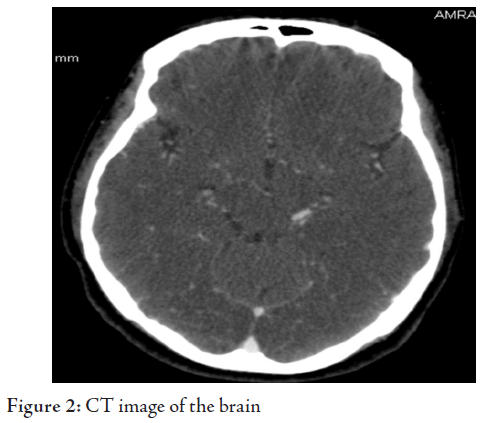

glucose 5.04 mmol, LDH 542. CT imaging of the brain showed hypodensity of

posterior cerebral whitematter. (Figs. 1, 2)